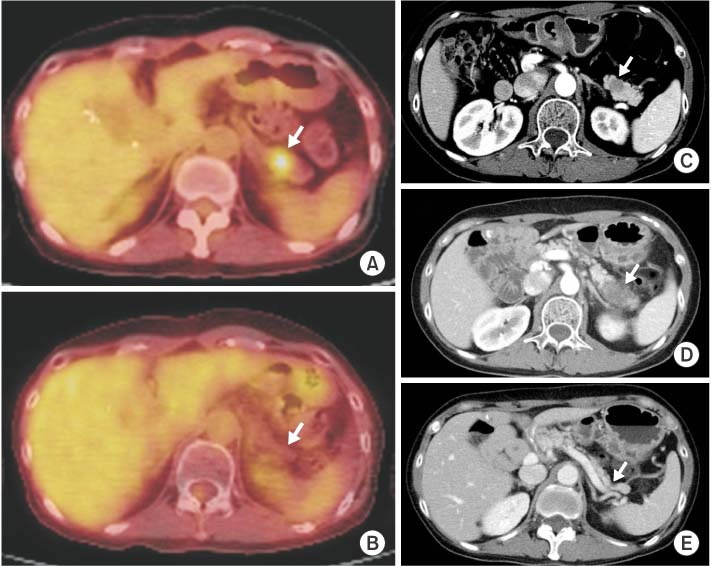

A 37-year-old woman was diagnosed with invasive ductal carcinoma of the right breast (Fig. 1). She underwent a total mastectomy and axillary lymph node dissection in May 2003. The tumor measuring 1.1 cm had no nodal or distant metastasis (pT1N0M0, stage I according to the 7th American Joint Committee on Cancer). Also it was an estrogen receptor-negative, progesterone receptor-negative and HER2-positive tumor with low Ki-67 index (5%), as determined by immunohistochemistry assay. She received six cycles of adjuvant chemotherapy (cyclophosphamide, methotrexate, and 5-fluorouracil). In January 2007, a solitary pulmonary nodule, which was 1.8 cm in diameter, was detected on chest computed tomography (CT) (Fig. 2A); it was confirmed to be a metastasis from the breast via percutaneous needle aspiration. There was no other distant metastasis except for a single mass in the right lung on 18F-fluorodeoxyglucose positron emission tomography-CT (18F-FDG PET-CT) (Fig. 2B). Lobectomy of the right lower lobe was performed via open thoracotomy (Fig. 2C, D). Six cycles of paclitaxel plus trastuzumab were then administered, followed by 35 cycles of trastuzumab until progression. In March 2009, the pancreatic lesion was detected on 18F-FDG PET-CT with standardized uptake value of 7.7 (Fig. 3A). The mass was observed as a low attenuating lesion (1.5 cm) in the pancreatic head on a CT scan of the abdomen and pelvis (Fig. 3B). A pylorus-preserving pancreaticoduodenectomy was performed, and metastatic infiltrating ductal carcinoma was confirmed (Fig. 3C, D). She received two cycles of combination chemotherapy with doxorubicin and cyclophosphamide. And newly appeared small lymph nodes at the mesentery were detected, considered disease progression. Therefore, eight cycles of gemcitabine and navelbine were administered from June to November 2009. However, in May 2010, a metastatic lesion of the pancreatic tail was newly detected on 18F-FDG PET-CT (Fig. 4A), and the nodules in the mesenteric lymph nodes became unremarkable. This pancreatic tail lesion was 1.5 cm in diameter on the CT scan (Fig. 4C). She received image-guided radiation therapy (IGRT) of 45 Gy in three fractions but the mass increased to 4 cm, as observed on a CT scan obtained the next month (Fig. 4D). Lapatinib plus capecitabine regimen was initiated in July 2010, and these treatments were continued over 4 years. The pancreatic tail lesion disappeared on an 18F-FDG PET-CT scan obtained in January 2011 (Fig. 4B) and on an abdominal-pelvic CT scan obtained in May 2011 (Fig. 4E). The pancreatic tail mass has been in complete response for 48 months since May 2011. A 25% dose reduction of lapatinib from the original dose was done in only one cycle due to grade 2 hyperbilirubinemia. The dose of capecitabine was reduced by 25% from the 3rd to 26th cycles due to grade 2 diarrhea and has been administered at 60% of the original dose from the 27th cycle until now.

Fig. 4

Radiologic findings of pancreatic tail lesion with complete response. The pancreatic tail mass has been initially shown as a hypermetabolic lesion (standardized uptake value, 3.3) on an 18F-fluorodeoxyglucose positron emission tomography computed tomography (18F-FDG PET-CT) scan (A) and as a low-attenuating lesion (1.5 cm) on an abdominal-pelvic CT scan (C). After image-guided radiation therapy of 45 Gy, enlarged mass is shown (D). However, after combination chemotherapy with lapatinib and capecitabine, this pancreatic tail mass disappeared on 18F-FDG PET-CT (B) and CT (E) scans.